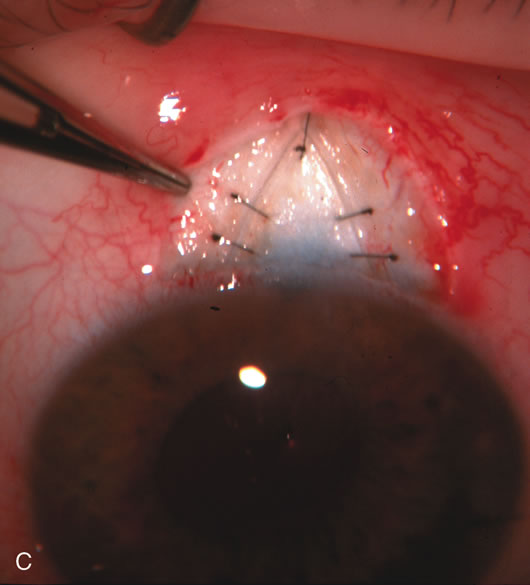

Fig. 7. Phacotrabeculectomy adjacent to a failed filter in cataractous eye. The ability to combine small-incision cataract extraction with trabeculectomy all through the same incision adjacent to the failed filter allows the surgeon to work in a familiar superior area. Avoiding incisions into the existing bleb decreases conjunctival buttonholes, hypotony, operating room time, and subconjunctival bleeding. A. Appearance of failed bleb with exposure of superior temporal quadrant gained with a corneal traction suture. B. Prepare a limbus-based conjunctival flap and a scleral flap. C. This bleb is at high risk to fail again justifying the need for MMC, 0.2 mg/cc applied on a pledget for 4 minutes. D. Insert the keratome and perform phacotrabeculectomy in the usual fashion.

The inflammation associated with lens extraction at any site usually causes complete failure of a marginal functioning bleb. In addition, pressure reduction by medical means is usually minimal in these recalcitrant cases, and combined surgery is indicated. In the past, these cases were approached with large-incision ECCE, clear corneal cataract incision, and bleb revision. Drawbacks included those mentioned earlier for large incision clear corneal cataract extraction, and bleb revision is often associated with conjunctival buttonholes, wound leaks, subconjunctival hematoma, destruction of friable sclera, and associated hypotony. With the advent of modern-day cataract surgery, a phacotrabeculectomy is often possible adjacent to the failed filter (Fig. 7). The ability to combine cataract extraction with implant and filtration surgery all through the same small incision has greatly improved outcomes for patients with marginal preoperative filters. There are several other viable options in this case. If the surgeon elects to remove the cataract through a temporal clear corneal incision, the bleb may be revised or a new adjacent filter fashioned. As mentioned earlier, revising a failed filter is technically challenging. If the surgeon believes it is not feasible to revise the filter or fashion a new one, a glaucoma drainage implant is a reasonable option combined with temporal lens extraction.172